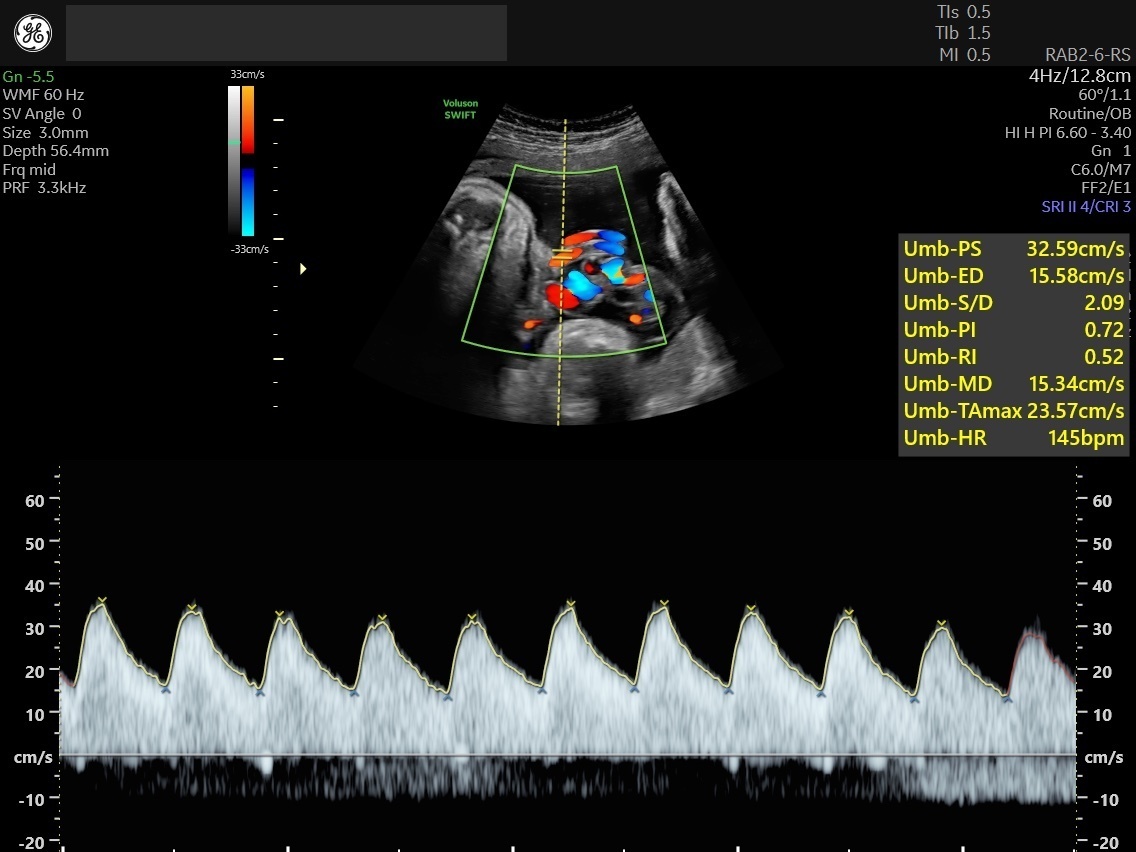

Umbilical Artery Doppler Reference Ranges Radiology World

Doppler Scan